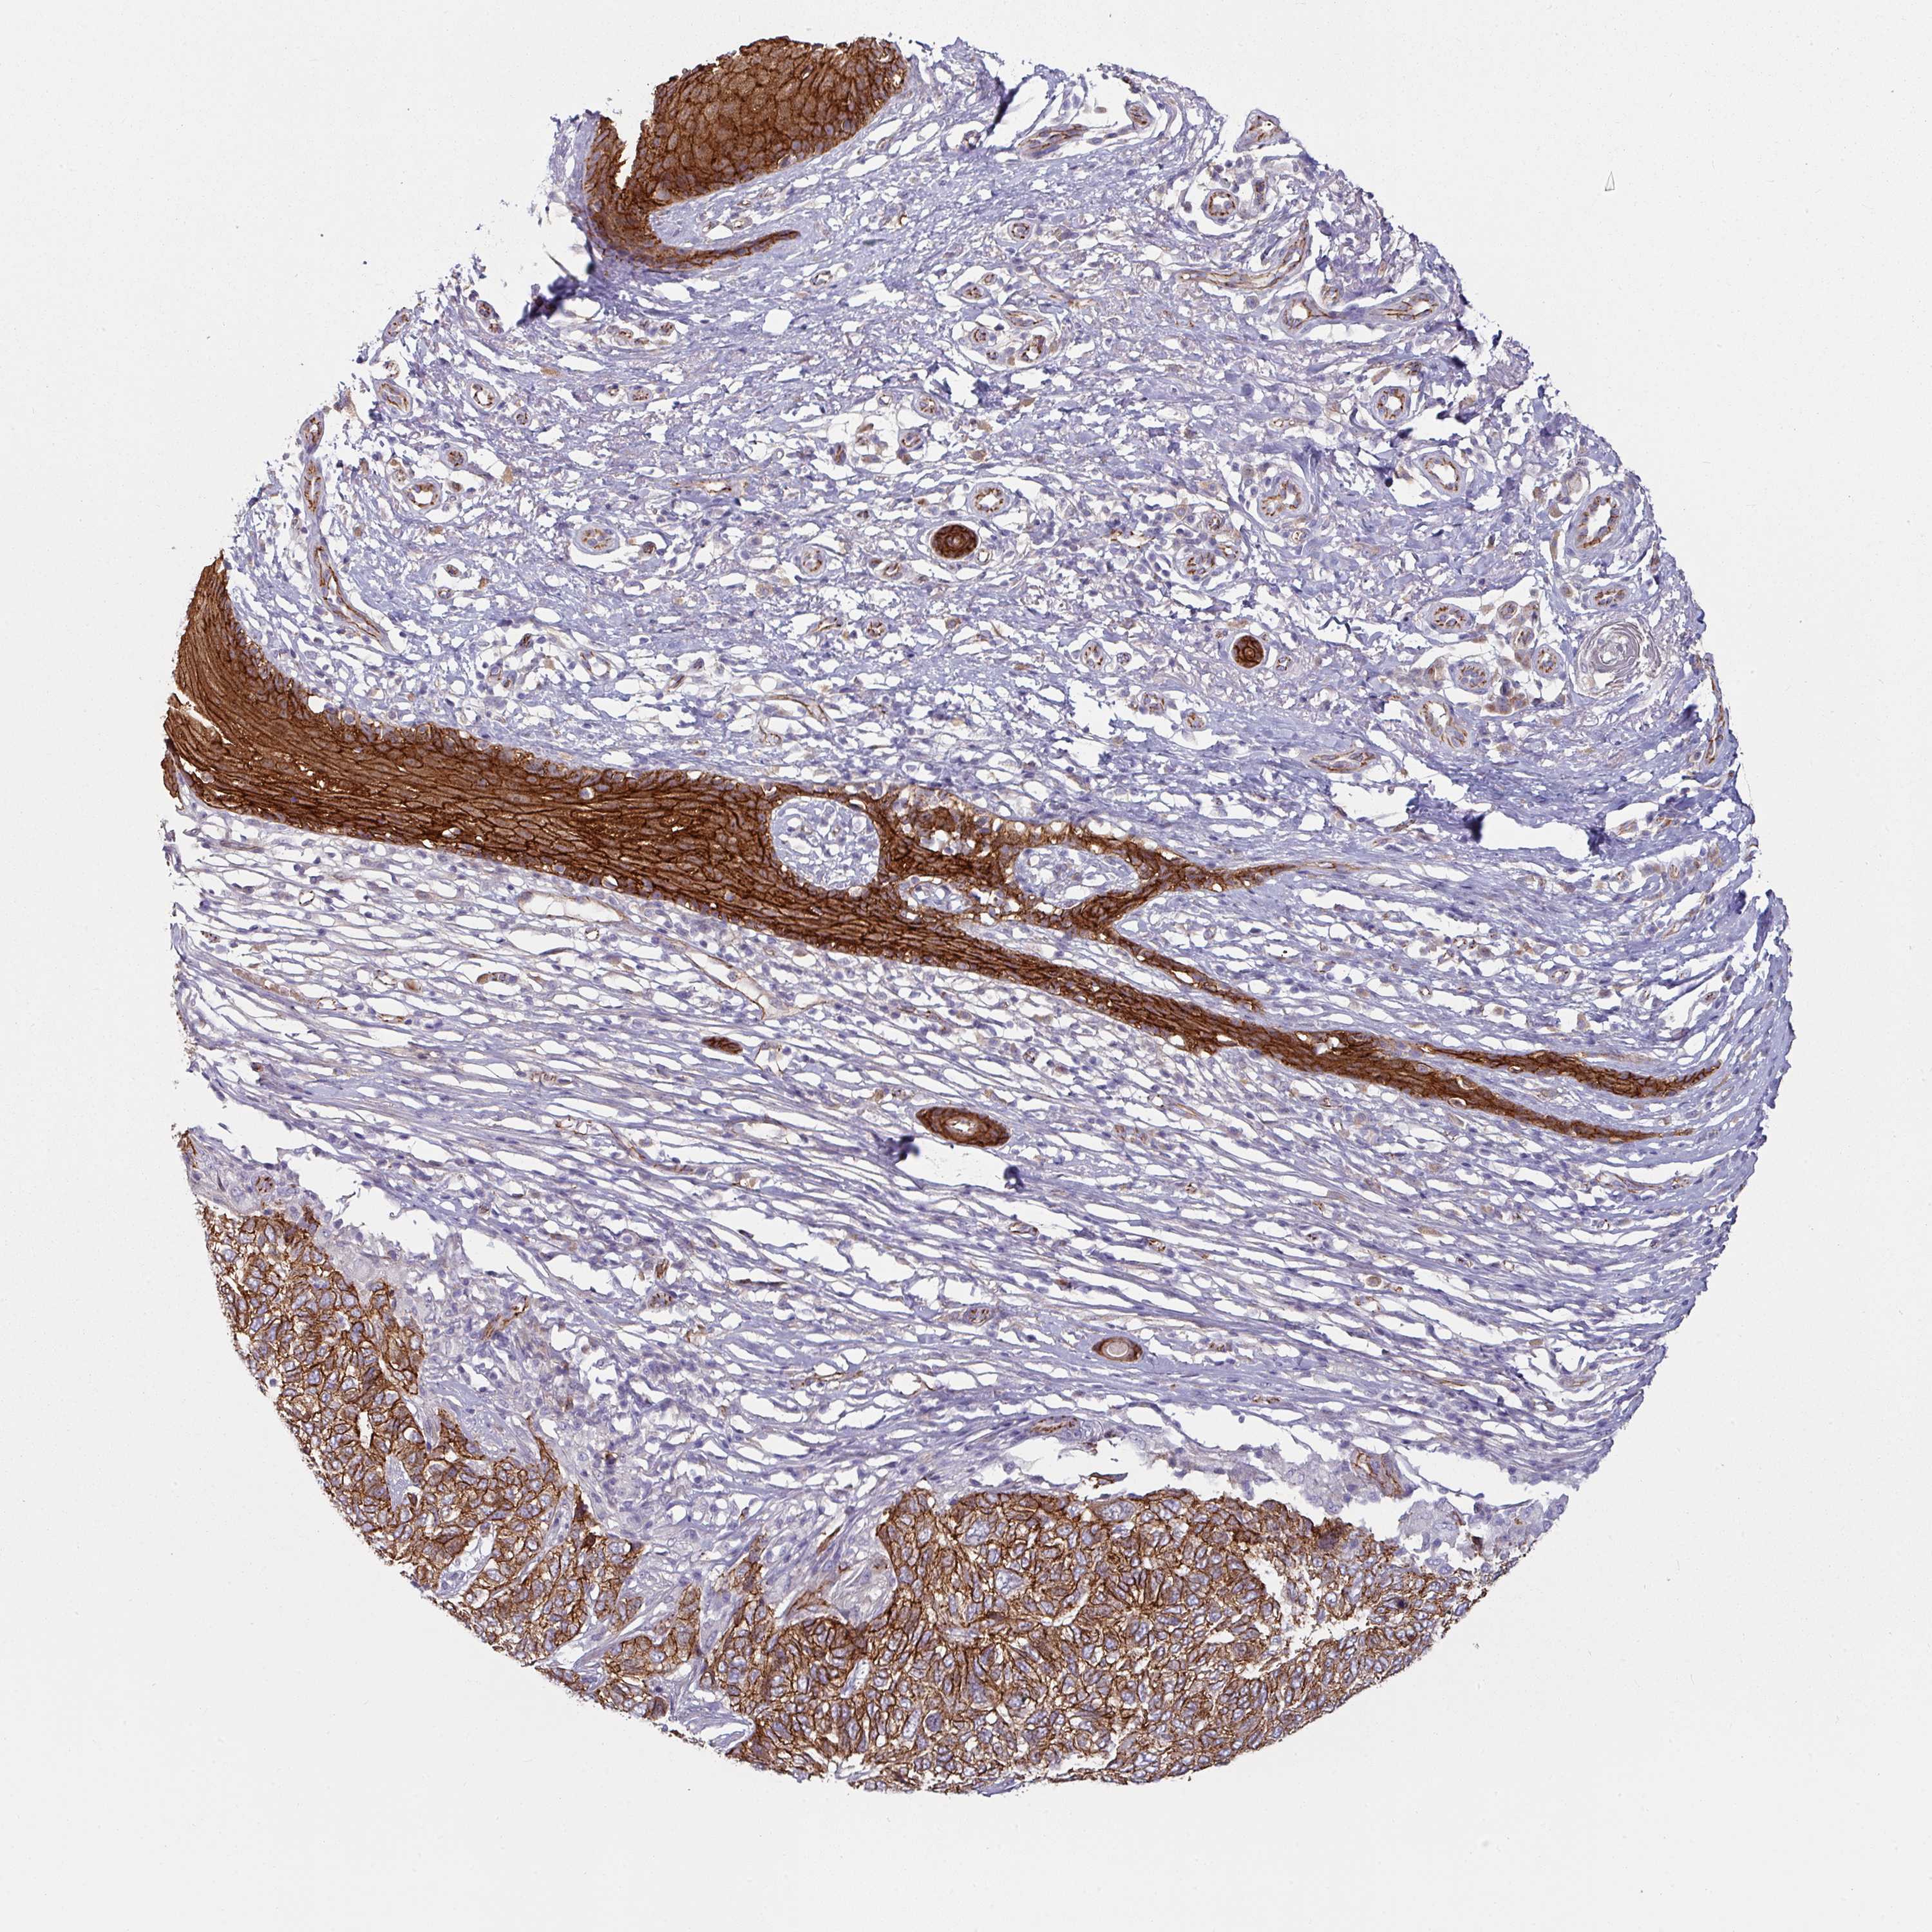

SKIN CANCER - Protein expressioni

A mouse-over function shows sample information and annotation data. Click on an image to view it in a full screen mode. Samples can be filtered based on level of antibody staining by selecting one or several of the following categories: high, medium, low and not detected. The assay and annotation is described here.

Antibody stainingi

Antibody staining in the annotated cell types in the current human tissue is reported as not detected, low, medium, or high, based on conventional immunohistochemistry profiling in selected tissues. This score is based on the combination of the staining intensity and fraction of stained cells.

Each image is clickable and will lead to virtual microscopy that enables deeper exploration of all samples and also displays staining intensity scores, fraction scores and subcellular localization as well as patient and tissue information for each sample.

Antibody HPA032047

Antibody CAB002139

Basal cell carcinoma

Squamous cell carcinoma, NOS

Squamous cell carcinoma, metastatic, NOS